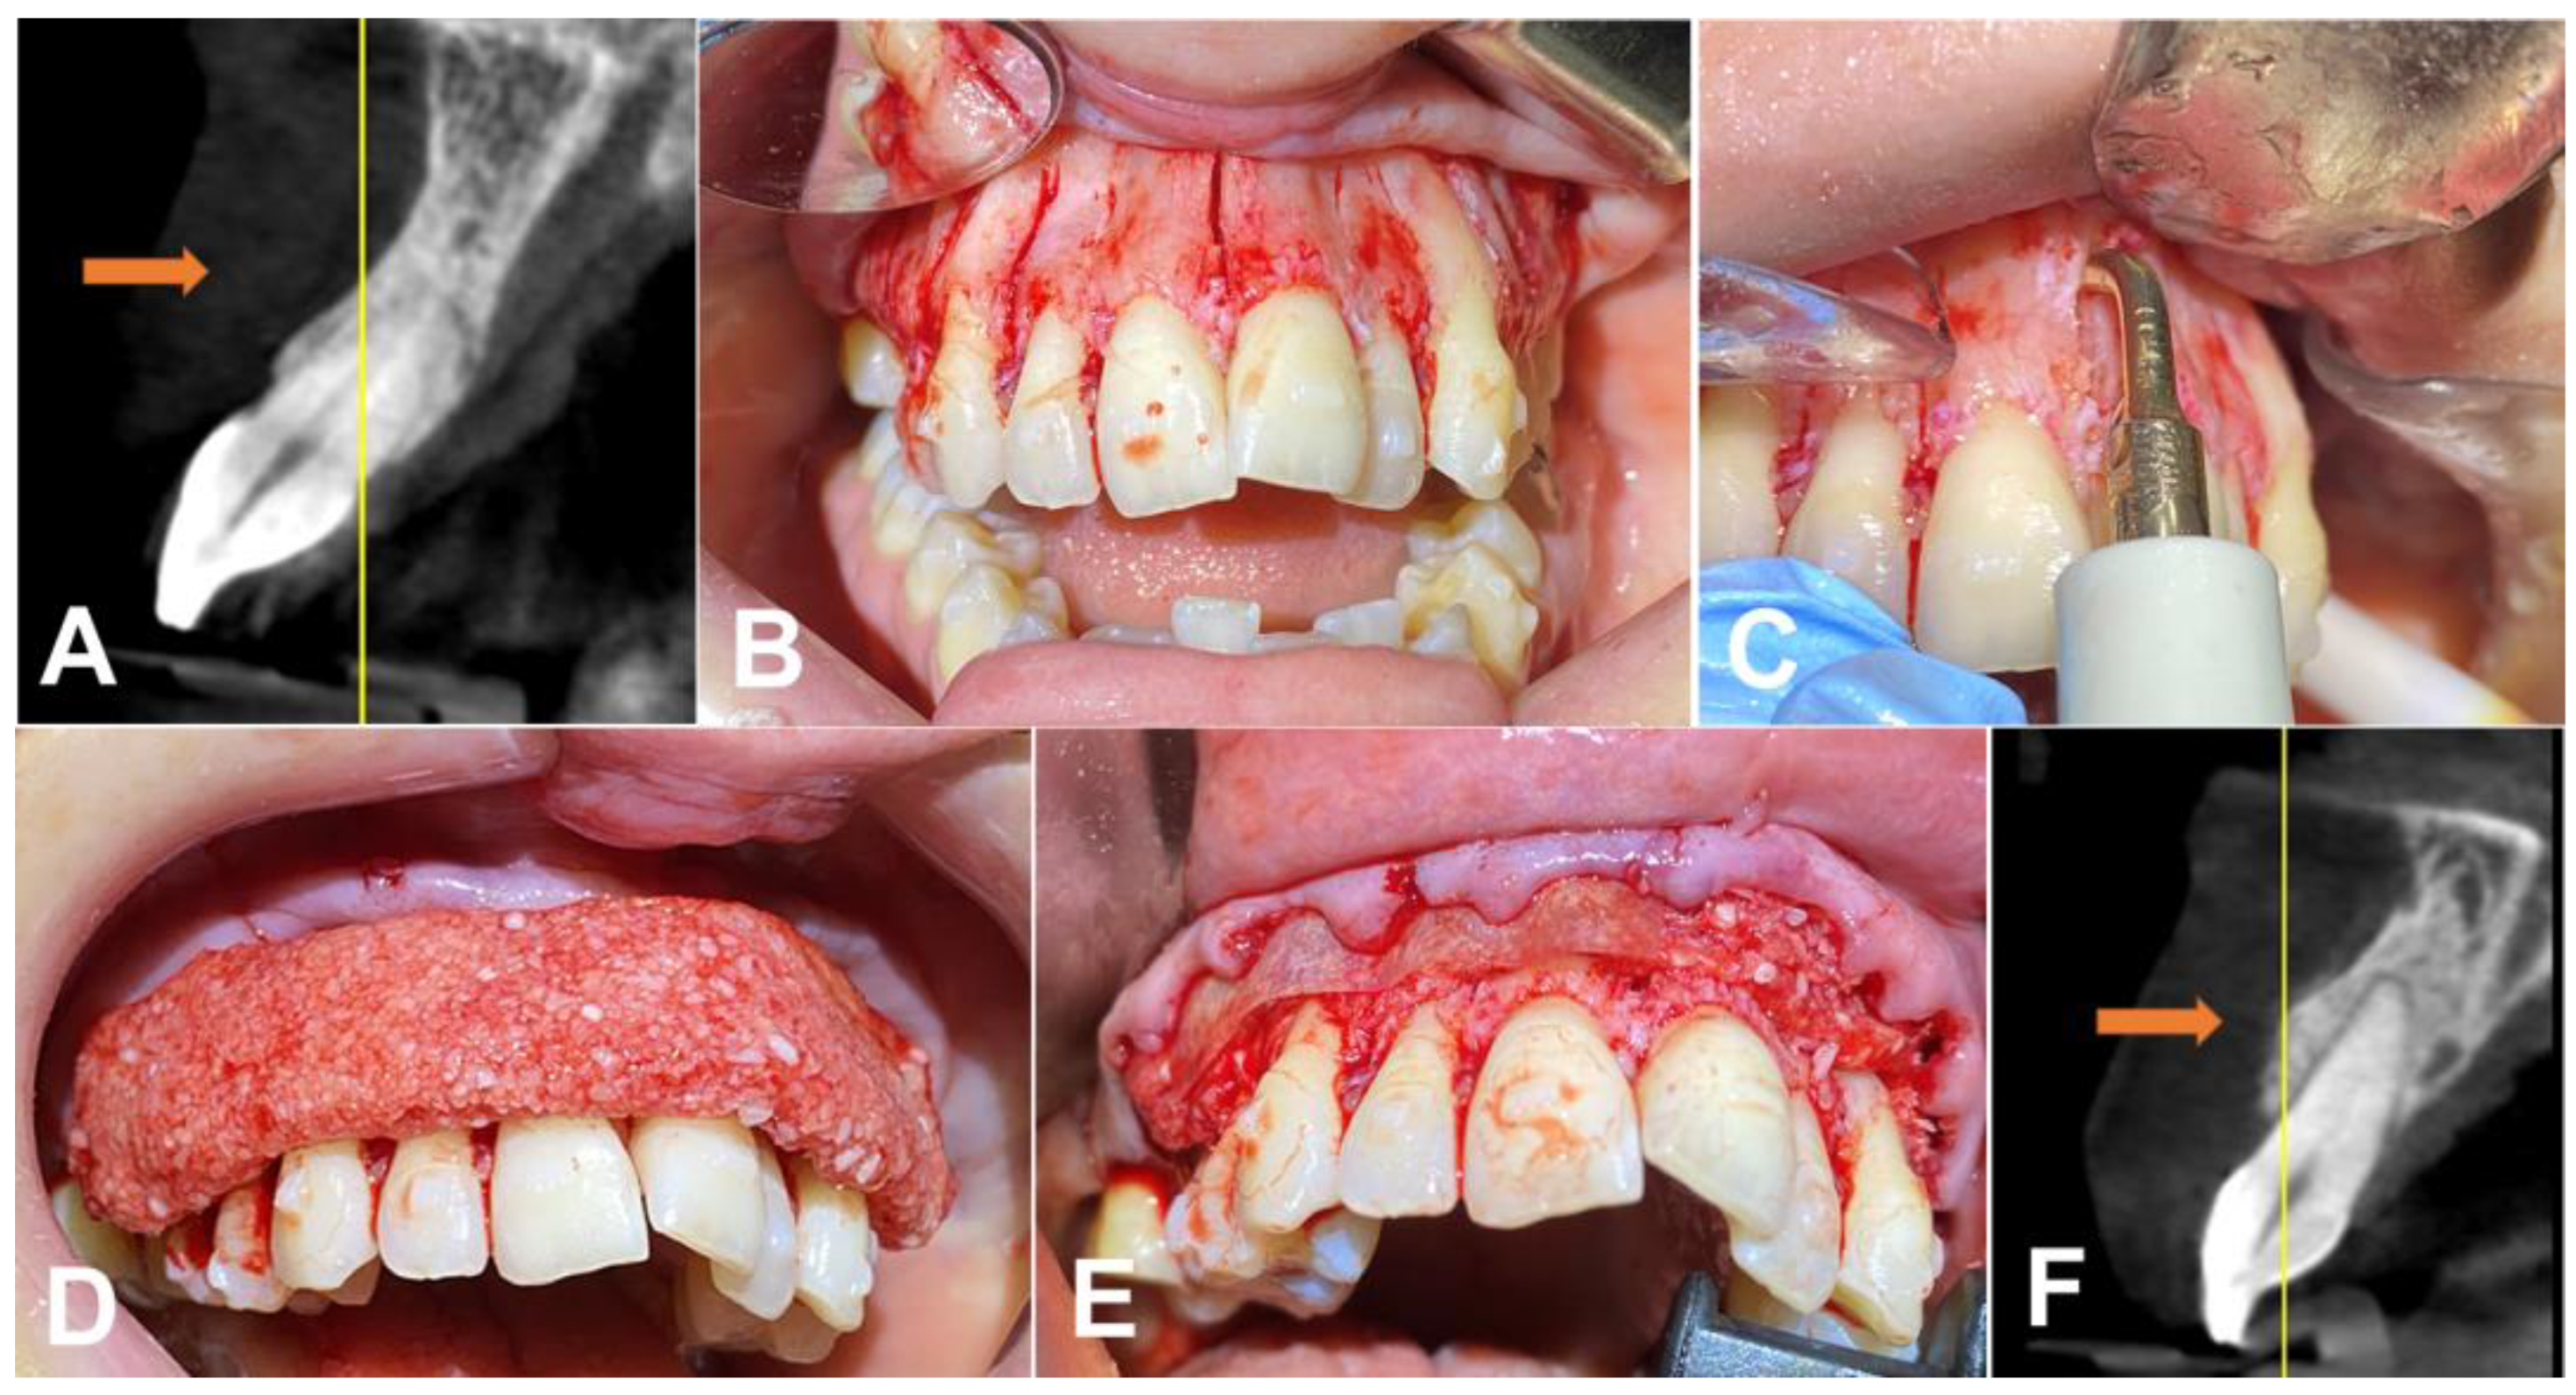

Both patients were given the opportunity to ask questions and seek clarification on any concerns they may have had. After doing so, they willingly agreed to proceed with their respective treatment plans. The dental team took all the necessary steps to obtain formal agreement from the patients, ensuring that the process was thorough and complete. This approach was taken to ensure that the patients fully understood the consequences of their decisions and were confident in their choices. The patients underwent a PAOO procedure to correct the malocclusion. Before the surgery, the patients underwent a cone beam computed tomography (CBCT) scan to assess their bone structure so a customized Invisalign treatment plan could be developed (Figure 1A). During the surgery, a piezoelectric motor (Piezosurgery®, Piezosurgery Inc., a Mectron Company, Columbus, OH, USA) with a straight tip (OT12) was utilized to create precise cuts in the cortical bone between the teeth. The cuts extended approximately 5 mm to the middle of the palatal bone raphe (Figure 1B,C). They were followed by bone decortication using a diamond tip (OT1). After making the cuts between the teeth, an allograft bone graft (Maxxeus®, Dayton, OH, USA) was placed over the area to enhance and strengthen the bone structure. In addition, an allograft membrane/barrier was placed on top of the bone graft to protect the area.

The bone graft was prepared using leucocyte–platelet-rich fibrin (L-PRF) [9,10]. In order to produce L-PRF, both red and white cap tubes were utilized to centrifuge the patient’s blood using a machine manufactured by Biohorizons® (AL, USA). Taking into account the centrifuge’s balance and the types of tubes used, a single centrifugation was performed to simultaneously produce the L-PRF membrane and Liquid L-PRF, following the “One Spin—Double Process” (a method by C.F.M.) (L-PRF protocol: ~700 RCF-max (~400 RCF-clot) for 8 min) [9,10]. After producing the L-PRF, the membranes were cut into smaller pieces and mixed with the bone graft. Subsequently, the Liquid L-PRF was incorporated into the graft, and after a waiting period of 4 to 6 min, the clot was integrated into the bone substitute, creating the “Sticky Bone” [9,10]. (Figure 1D), which facilitated the handling of the graft material. Following the bone graft and membrane (Pericardium, Maxxeus®, OH, USA) placement (Figure 1F) on top of the pericardium membrane, the L-PRF membrane was placed, and primary closure was achieved using Polytetra Fluoro Ethylene (PTFE) 4–0 sutures (Ethicon®, Johnson & Johnson, New Brunswick, NJ, USA).

Figure 1. (A) Initial representative image of the CBCT before the bone graft, with an arrow indicating the thickness of the wall of the bone.; (B) cuts in the cortical bone between the teeth; (C) deep approach using the surgical tip in the palatal bone raphe; (D) bone graft (sticky bone) placed on top of the native bone after decortication and cuts; (E) membrane placed on top of the graft; and (F) representative image of the bone wall one year after treatment (arrow).